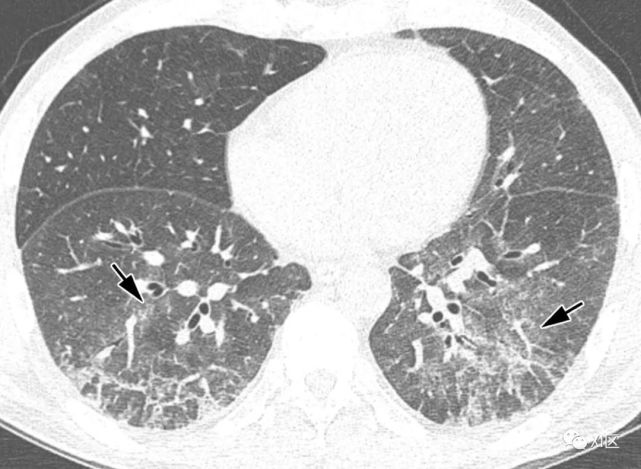

图片

图17 50岁女性,因HMPV引起的肺炎,表现为发烧、咳嗽和咳痰。

(上) 胸片显示右肺多结节性气腔影(箭头)。在同一天获得的薄层(1mm)轴位(中)和冠状位(下)重建(5mm)的胸部CT图像显示沿支气管血管束的多个不明确的中心小叶结节(箭)或GGO(箭头),两肺轻度支气管壁增厚,尤其是右肺。